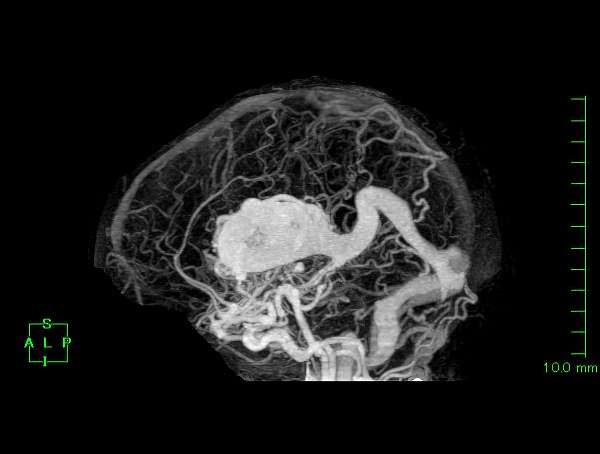

脳血管撮影

手術前

手術後